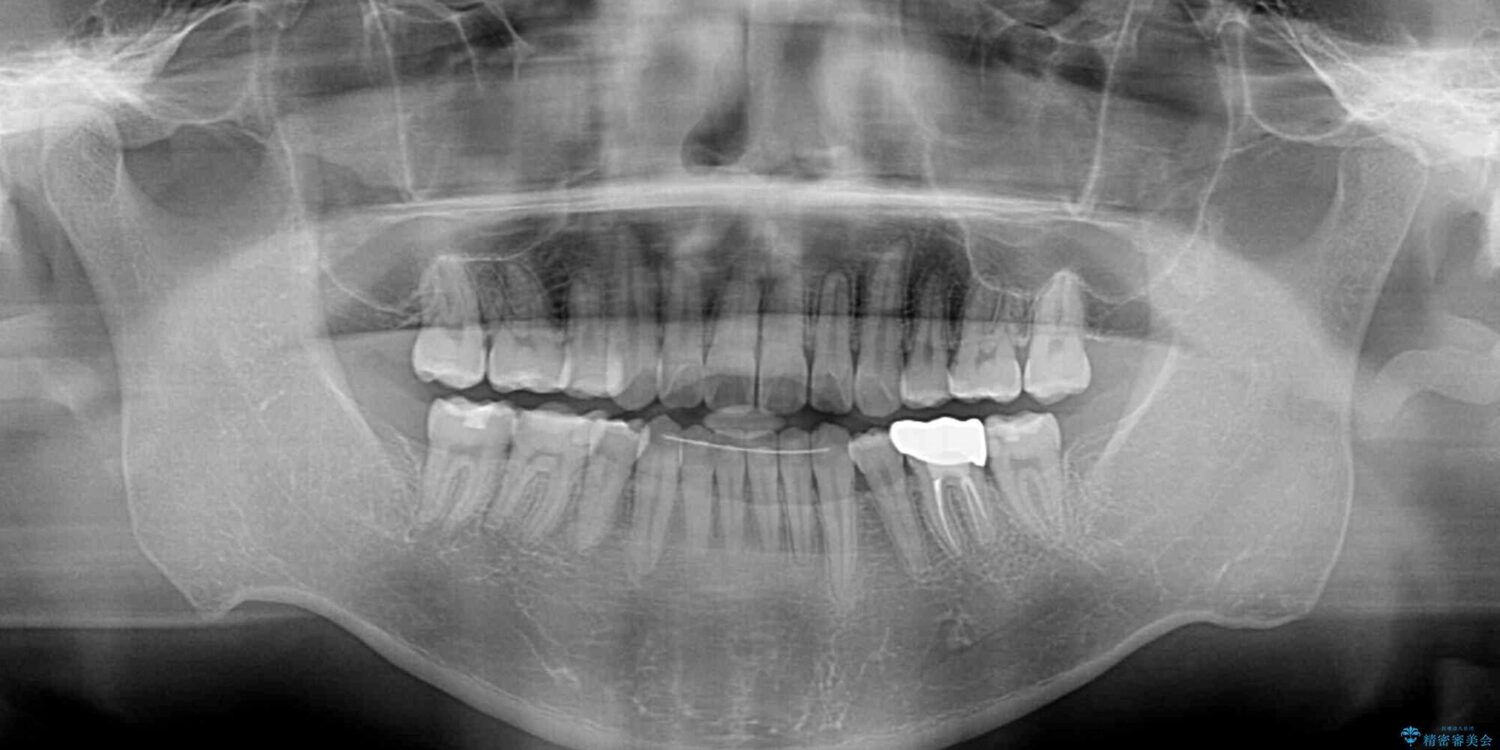

高校時代に行った抜歯矯正が後戻りをしたとのことで来院された患者様です。

治療計画

再矯正であることから、目立ちにくい装置を希望されたため、インビザラインにて矯正治療を行うこととしました。

治療後について

下顎骨が左側に変位しているため、正中が合わないことは予想できましたが、歯列が整った後も咬み合わせが安定せず、咬み合わせを落ち着かせるために1年以上の期間を要しました。

噛みにくさの改善に時間がかかってしまうことがインビザラインの欠点の1つといえます。

治療前

• 後戻りでデコボコの前歯 インビザライン矯正治療 治療前画像